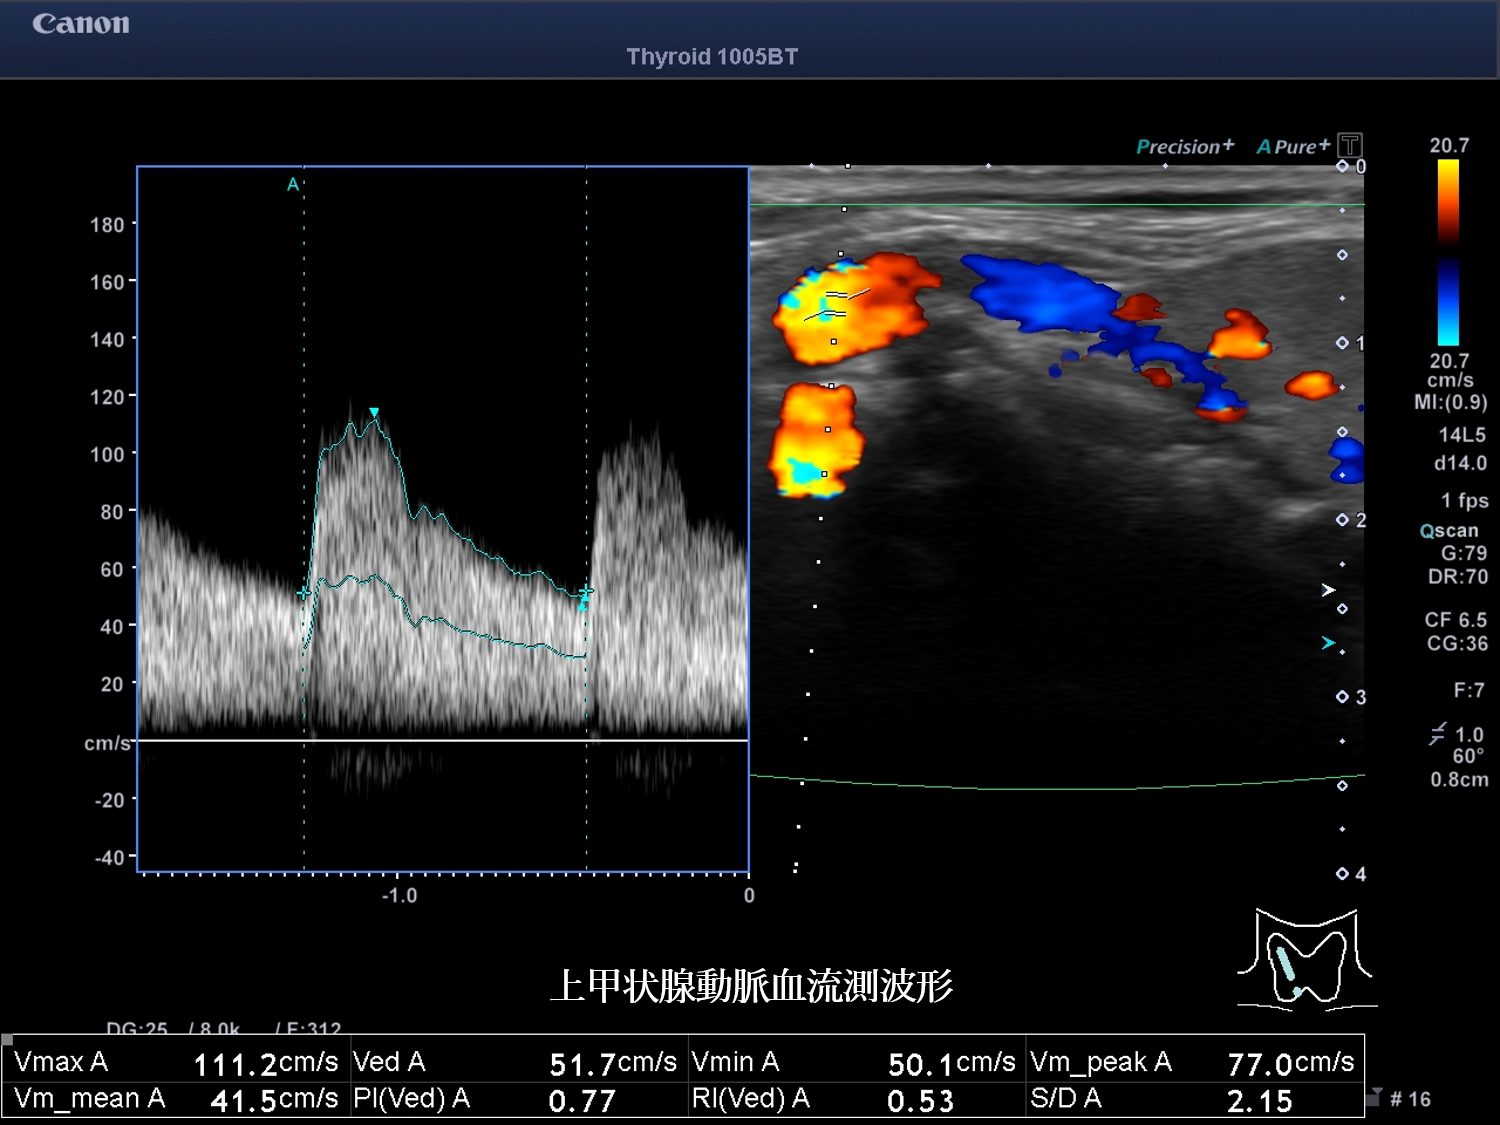

甲状腺超音波 動画 右葉横断像 カラー(No20-21_A)

甲状腺超音波画像 画像1(No20-21_1)画像2(No20-21_2)画像3(No20-21_3)

誤っている超音波所見はどれか。

④ 甲状腺内血流は増加している

⑤ 低エコー域内の血流低下を認める

超音波所見より考えられる超音波診断はどれか。

① バセドウ病